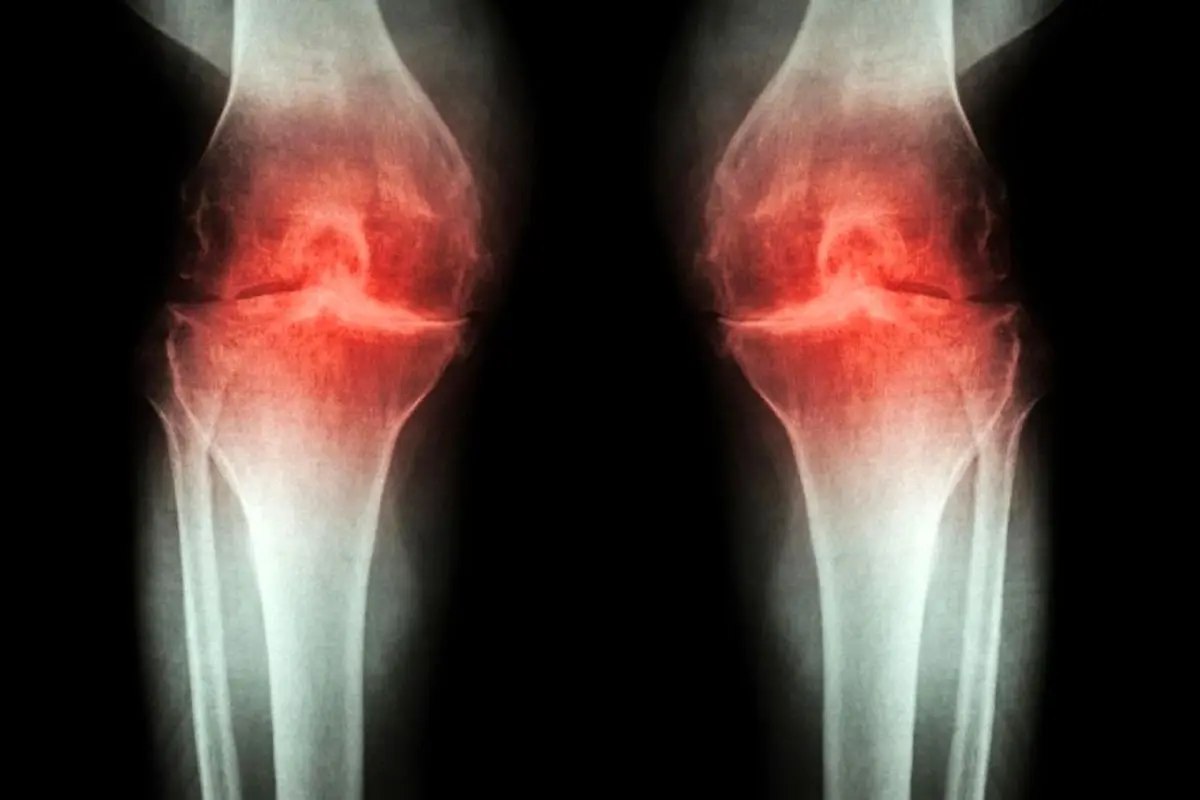

روش درمان آرتروز با شناسایی سیگنال درد

پارسینه: استئوآرتریت میتواند یک بیماری ناتوان کننده باشد و حرکات را همراه با درد کند.

این بیماری زمانی شروع میشود که غضروف مفاصل فرسوده میشود و با ساییدگی فزاینده استخوانها روی یکدیگر، باعث درد میشود. درد را میتوان با استفاده از داروهای بدون نسخه یا تغییر شیوه زندگی کنترل کرد؛ اما میتواند با پیشرفت بیماری همچنان یک مشکل باقی بماند. برای یافتن داروهای طولانی مدت بهتر برای مدیریت درد مزمن، دانشمندان مسیرهای مولکولی را بررسی کرده اند که درد را به مغز منتقل میکند.